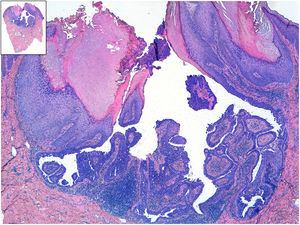

HistopatologíaEl examen histológico mostró numerosas formaciones quísticas invaginadas desde la epidermis y varias lesiones papilomatosas exofíticas cubiertas por epitelio escamoso con hiperqueratosis. La zona más profunda estaba constituida por un epitelio de doble capa (la más interna formada por células cilíndricas y la más externa por células mioepiteliales cuboidales). El estroma subyacente era rico en células plasmáticas (fig. 2).

El diagnóstico diferencial lo tenemos que realizar con el carcinoma basocelular, escamoso o con una lesión quística1. La biopsia es necesaria para confirmar el diagnóstico. El estudio con hematoxilina-eosina revela unas proyecciones epiteliales hacia la dermis con estructuras tubulares que conectan con la superficie y están constituidas por una doble capa de células. La más externa formada por células cuboidales y la más interna por células cilíndricas. El estroma es rico en células plasmáticas2.